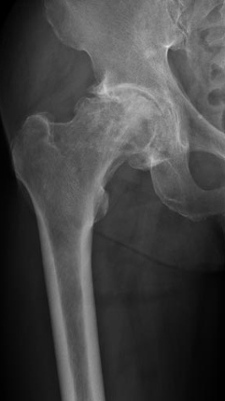

Acute Collapse of Femoral Neck of Hip